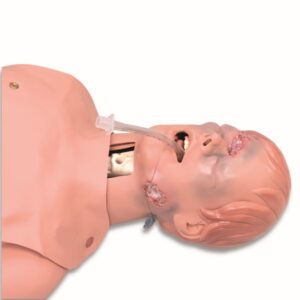

Simulaids Ausculation Trainer

Ausculation Trainer, Practice Board and Smartscope™

Ausculation Trainer, Practice Board and Smartscope™